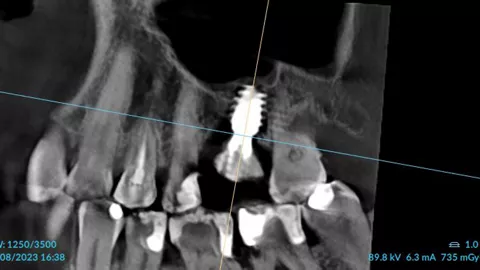

3a. 3b. 3c. 3D volumetric diagnosis and planning of implant therapy.

3a

3b

3c